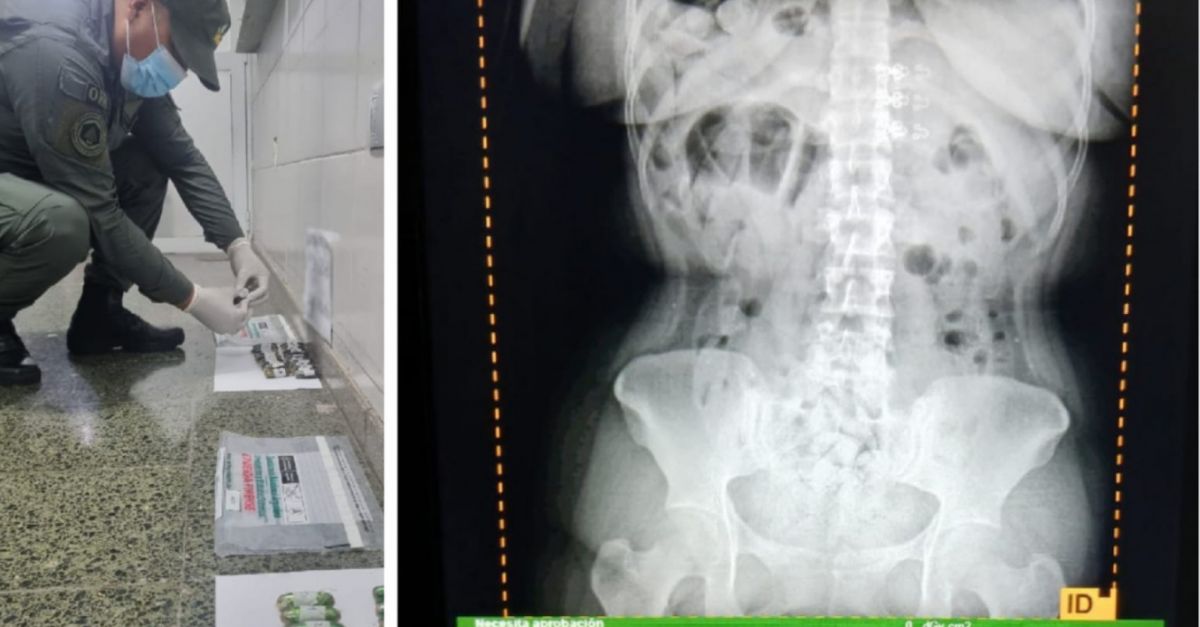

Al momento de la inspección, los funcionarios notaron que las pasajeras manifestaron molestias abdominales. Ante las altas posibilidades de estar frente a un hecho ilícito, los gendarmes realizaron el traslado de las mujeres involucradas hacia el Hospital de Trancas para realizar las placas radiográficas en donde pudieron observar la presencia de cápsulas.

Teniendo en cuenta la gravedad de la situación debido a que es un riesgo para la salud, trasladaron a las ciudadanas hasta Centro de Salud Zenón Santillán, en la ciudad de San Miguel de Tucumán, a en donde evacuaron un total de 198 cápsulas.